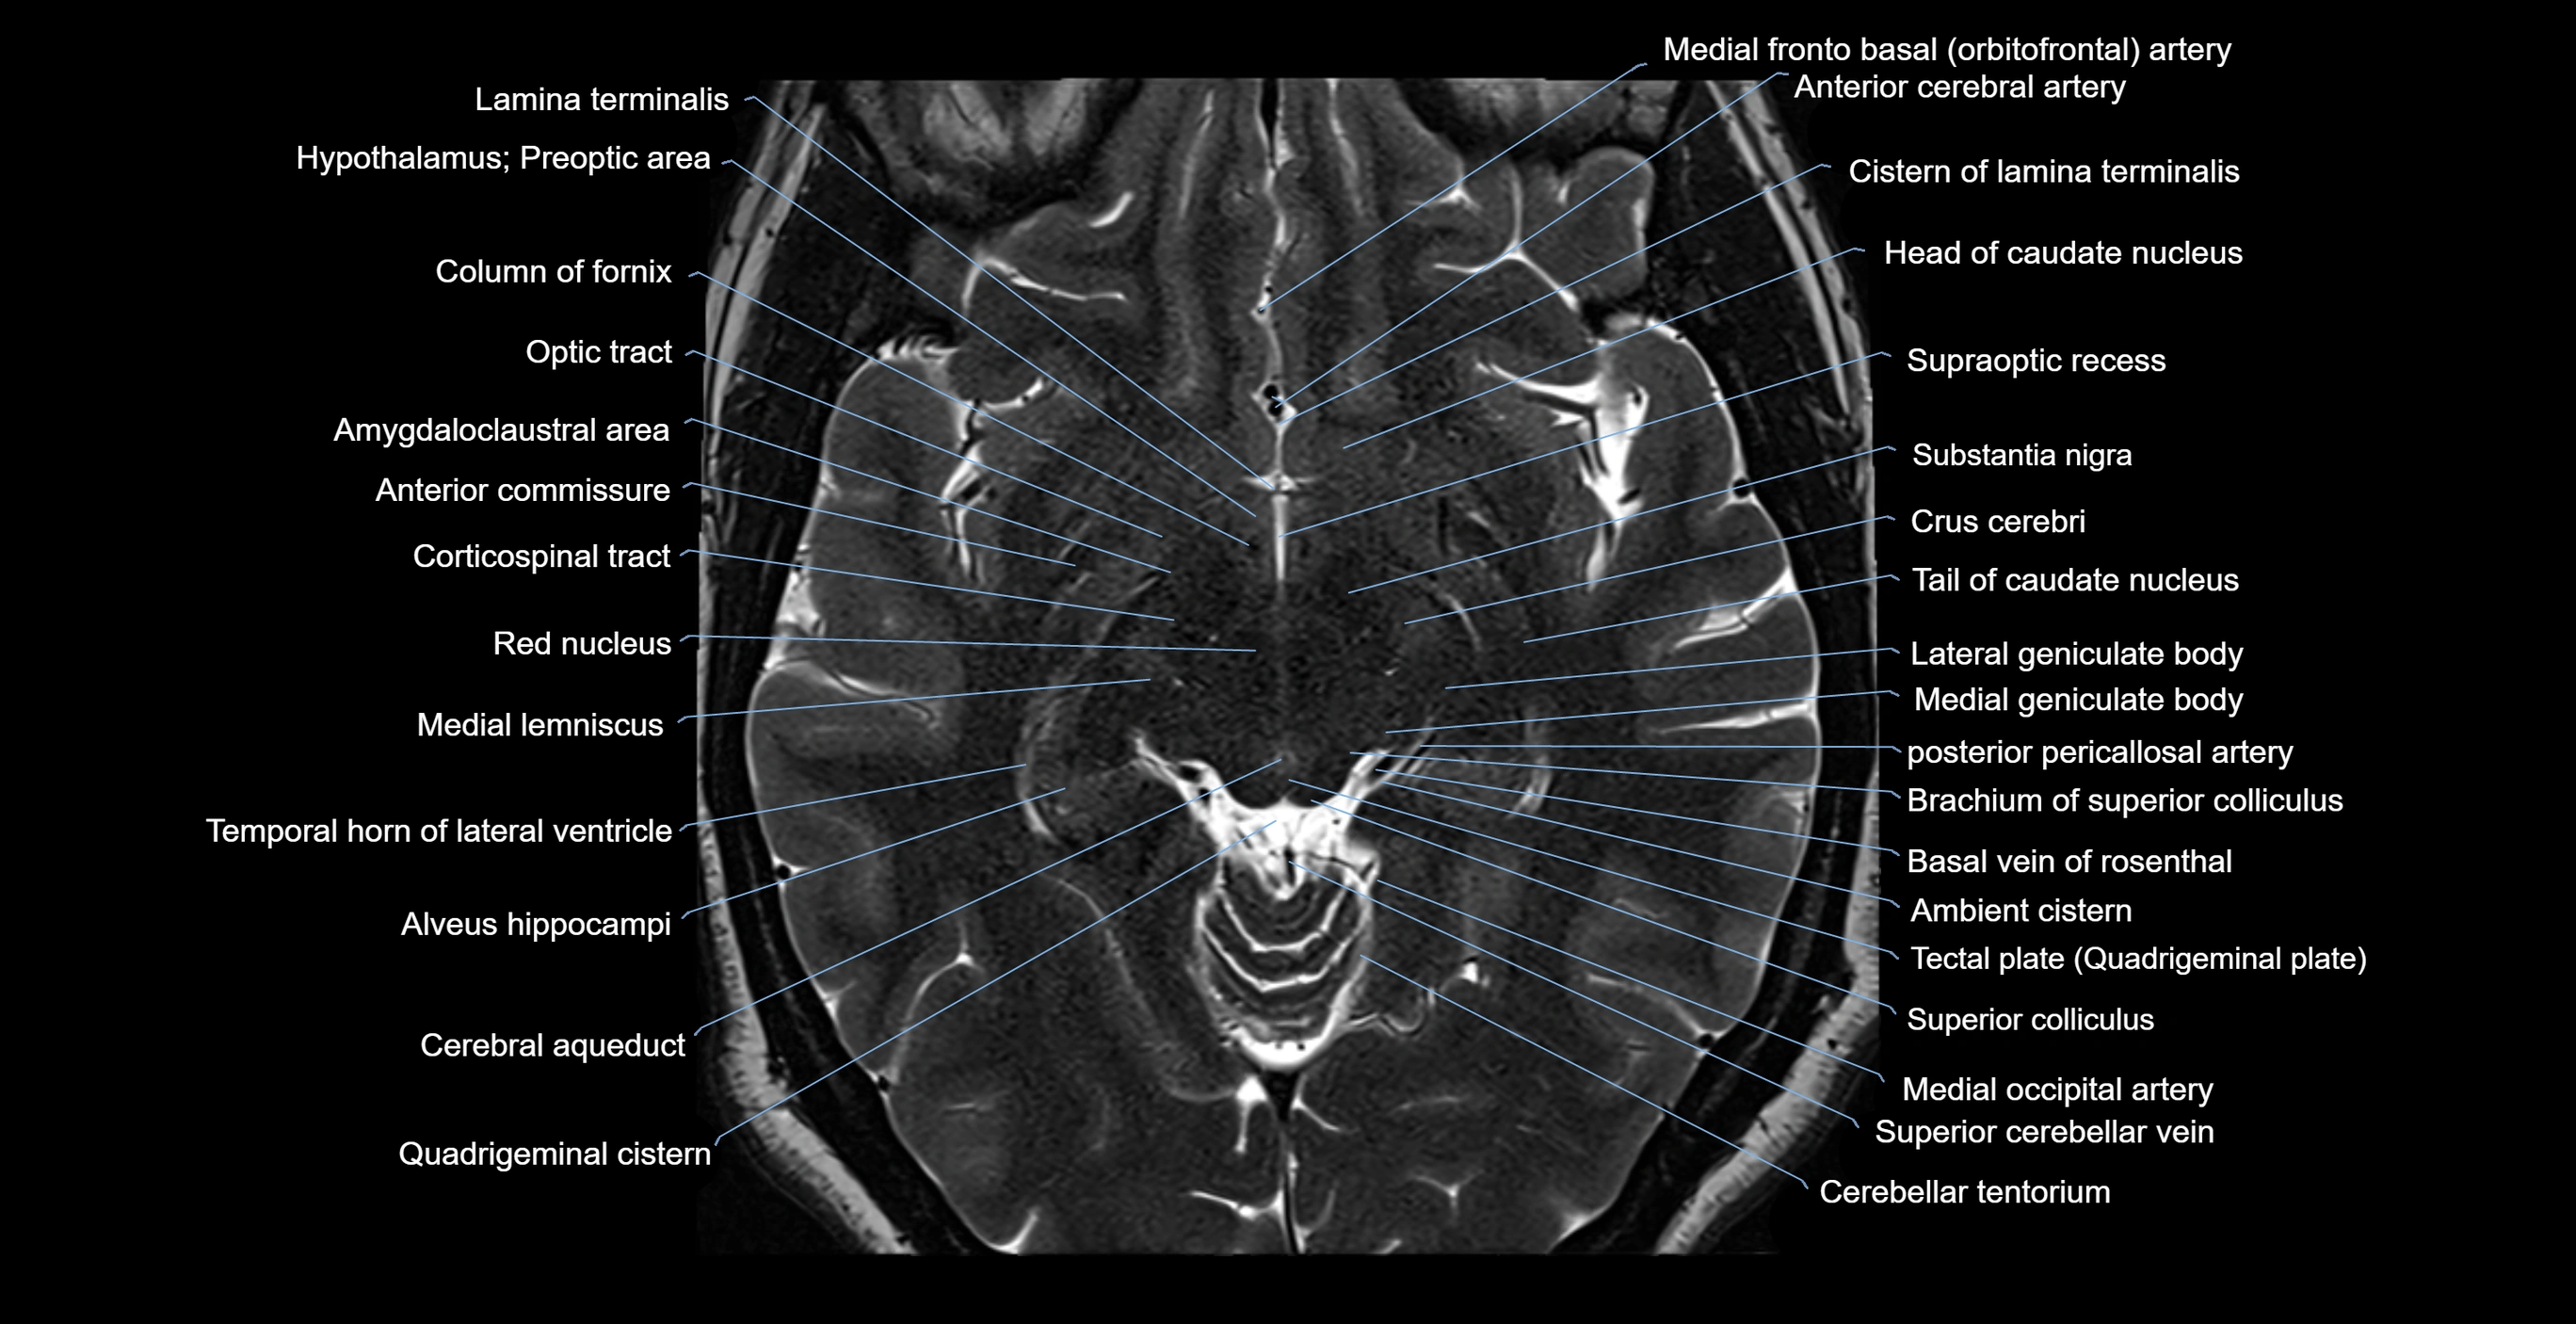

- Amygdaloclaustral area

- Anterior commissure

- Brachium of superior colliculus

- Cerebellar tentorium

- Cerebral aqueduct

- Cerebral crus

- Column of fornix

- Corticospinal tract

- Crus cerebri

- Head of caudate nucleus

- Hypothalamus

- Infundibular recess

- Lateral geniculate body

- Medial geniculate body

- Medial lemniscus

- Medial occipital artery

- Optic tract

- Quadrigeminal cistern

- Red nucleus

- Substantia nigra

- Superior colliculus

- Supraoptic recess

- Tail of caudate nucleus

- Tegmentum of midbrain

- Temporal horn of lateral ventricle